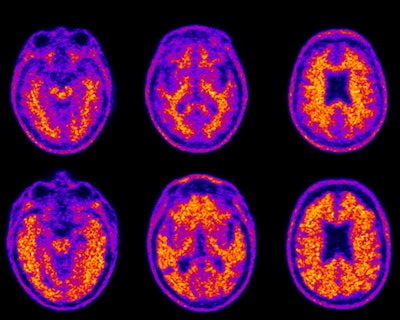

Florbetapir-PET scans show the brain of a cognitively healthy 74-year-old (top row) who demonstrated average financial skills, compared with an 86-year-old with mild Alzheimer's disease (bottom row) who demonstrated impaired financial skills. The bottom scan is positive for amyloid plaques, highlighted in yellow and orange throughout the brain and extending to its edges. Images courtesy of Duke Health."There has been a misperception that financial difficulty may occur only in the late stages of dementia, but this can happen early and the changes can be subtle," said senior author Dr. P. Murali Doraiswamy, professor of psychiatry and geriatrics at Duke University, in a statement. "The more we can understand adults' financial decision-making capacity and how that may change with aging, the better we can inform society about those issues."